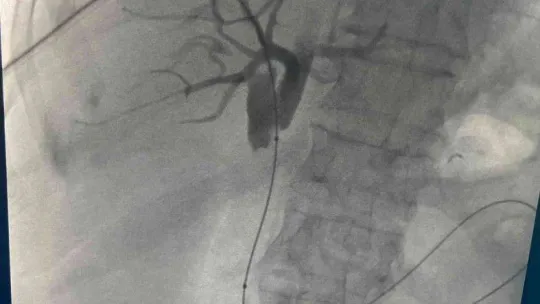

Prof. Dr. Ercan Kocakoç, bu yeni yöntemin tıp literatürüne Radyofrekans (RF) ablasyon olarak geçtiğini belirtti. Başta karaciğer olmak üzere vücudun birçok bölgesindeki tümörlerin ultrason, tomografi gibi görüntüleme yöntemlerinin kılavuzluğunda yakılarak tedavi edebilen, girişimsel radyolojik bir yöntem olduğunu söyledi. Prof. Dr. Ercan Kocakoç, önce safra kanalı içerisine basitçe ince plastik bir hortum yerleştirilerek, biriken safra sıvısının dışarıya alındığını dile getirerek, “Tümörün olduğu bölgedeki darlık, bir tel yardımıyla geçilebilirse önce balon ile bu bölge genişletilmeye çalışılır. Sonrasında ise stent denilen ince tellerden örülü metalik bir küçük borucuk yerleştirilerek dışarıda hortum olmadan safranın on iki parmak barsağına akması sağlanır” dedi.

Prof. Dr. Ercan Kocakoç ayrıca safra yolu kanserlerinin tedavisinde Endobiliyer RF ablasyon yöntemi ile de safra kanalı içerisindeki tümörün RF ablasyon ile yakıldığını kaydederek, “Bu yöntemde safra kanalındaki darlığın balon ile açılması, safra kanalı içerisinden RF (radyofrekans) ablasyon ile tümörün yakılması ve safra kanalına metalik stent yerleştirilmesi aşamaları vardır. Bu işlem safranın on iki parmak bağırsağına akmasını sağlayarak sarılıksız daha uzun bir ömür geçirilmesine katkı sağlar” şeklinde konuştu.

Prof. Dr. Ercan Kocakoç en son, 75 yaşında yurtdışından sarılık şikâyeti ile gelen, ana safra kanalında tümör bulunan ve ciddi kalp yetmezliği nedeniyle ameliyatı riskli olan bir hastasına bu yöntemi başarıyla uyguladıklarını dile getirdi. Yaklaşık 11 ay önce genel anestezi verilmeden sedasyon ile endobiliyer RF ablasyon tedavisi ve stent yerleştirilmesi işleminin gerçekleştirildiğini açıkladı. Sarılığı yaklaşık 1 hafta içerisinde normale dönen hastamız halen sarılık şikâyeti olmaksızın hayatına devam etmektedir.